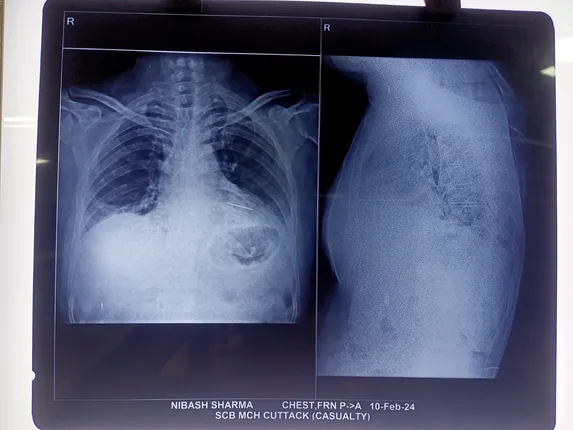

Cuttack: Doctors at the SCB Medical College and Hospital successfully removed a needle from the heart of a man here in Odisha.

According to reports, the 31-year-old man's chest was pierced with a needle while he was sleeping at his home. The needle got stuck in the left side of his heart leading to severe pain.

A team of doctors led by Cardiothoracic & Vascular Surgery Department HOD Prof. Dr. Manoj Kumar Pattnaik conducted the operation and successfully removed a 4.5-inch-long needle from the patient's heart.